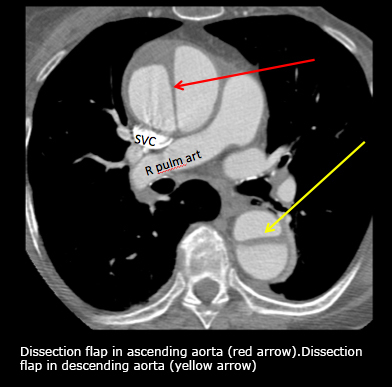

What is going on in this CT?

Ascending and descending aortic dissection